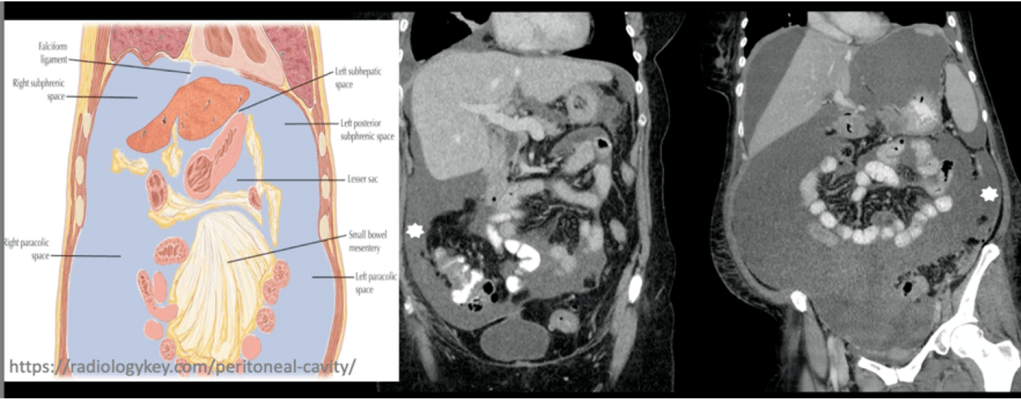

Answer: C) Fluid from the pelvis drains into the right para-colic space and subsequently ascends into the right sub-phrenic space.

Explanation: The peritoneal fluid from the pelvis can drain into the para-colic spaces, which are located next to the colon. Specifically, fluid from the pelvic cavity can move into the right para-colic space and then ascend into the right sub-phrenic space, facilitating the spread of infection or tumour. The para-colic spaces are important anatomical areas for the spread of diseases within the peritoneal cavity.

Option A is incorrect because the left sub-phrenic space does not directly communicate with the pelvis via the gastro-hepatic ligament. The peritoneal fluid’s movement is more complex and involves different routes for spread.

Option B is incorrect because the left sub-hepatic space is not directly continuous with the right para-colic space. The anatomical barrier between these regions limits direct spread of disease between the two spaces.

Option D is incorrect because Morrison’s Pouch, being the most dependent part of the abdomen, actually allows for the accumulation of fluid and can facilitate the spread of infection or tumour rather than preventing it. This pouch connects the right sub-hepatic space with the rest of the abdominal cavity, making it an important pathway for the spread of disease.

Option E is incorrect because peritoneal fluid does accumulate in the paracolic gutters, and it can indeed contribute to the spread of infection or tumour to the sub-phrenic spaces. The paracolic gutters provide a route for fluid and disease spread throughout the abdomen.